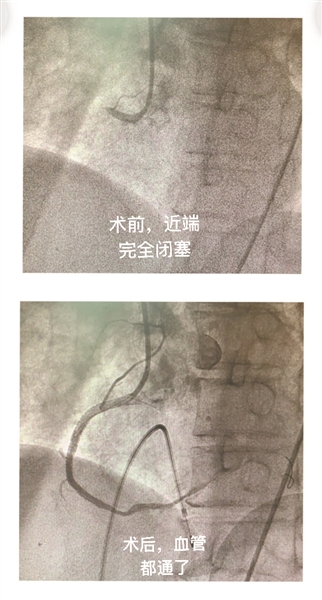

时间紧急,叶泽兵指挥直接绕行急诊科和CCU直达导管室。手术完成后,季老伯室颤消失,生命体征恢复,目前在普通病房恢复中。“真是一个奇迹!”叶泽兵表示,“这种情况我们都感觉很意外,患者已经82岁高龄了,也过了黄金抢救时间。没想到最后竟能起死回生了。”这个奇迹发生的关键,是尽最大的努力开通患者闭塞血管,恢复血流,这也是急性心肌梗死的救治关键,同时,术中的临时起搏器、IABP的辅助也起到了重要的作用。

在心内科团队通力合作和相关科室大力配合下,进行PCI术,顺利开通“犯罪血管”。手术成功完成,室颤消失,生命体征恢复,目前已经在普通病房恢复中。